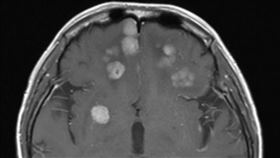

三陰性乳癌

三陰性乳癌難纏 3特性治療易不如預期